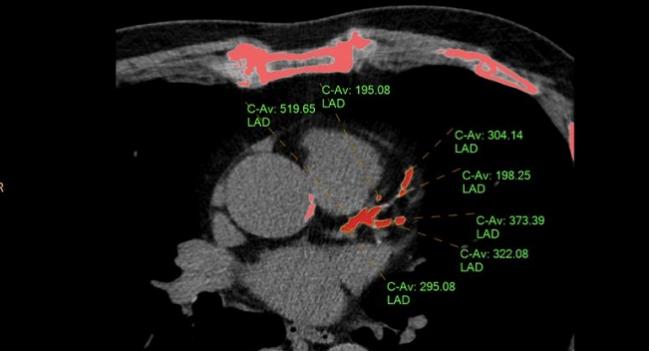

Speaking with TCTMD, Ryan Daly, MD (Franciscan St. Francis Health, Indianapolis, IN), zeroed in on the document’s position on CAC scoring, which he called “probably one of the strongest tools we have in our armamentarium for diagnosing coronary artery disease,” adding that a score of 0 identifies people who are not at risk or at very low risk with a “warranty period of 10 years or more.”

He questioned the USPSTF’s interpretation of the data, as well as their motives. “I think they're trying to do this in the most cost-effective manner, but [CAC] isn't terribly expensive,” said Daly. “They are worried about the potential risks in terms of downstream coronary angiography, but just because you have CAC doesn't mean you need a heart cath, and I think that's been shown time and time again.” Moreover, he continued, radiation dose is also minimal when the screening test is “done well,” typically less than 1.5 mSV. “So it's really not a substantial amount of radiation compared with other screening modalities,” Daly said.

Photo Credit: Ryan Daly